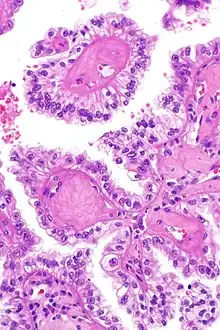

Micrograph showing the characteristic hyalinized papillary cores found in some hereditary leiomyomatosis and renal cell carcinoma syndrome-associated renal cell carcinomas. H&E stain.

The renal cell carcinoma tends to be of the papillary (type 2) form and tends to occur more commonly in women than men with this syndrome. These cancers present earlier than is usual for renal cell carcinomas (typically in the twenties and thirties) and to be at relatively advanced stages at presentation. Tumours have rarely been reported in children. These tumours occur in ~20% of those with this mutation suggesting that other factors are involved in the pathogenesis.

The renal cell carcinomas have prominent eosinophilic nucleoli surrounded by a clear halo.